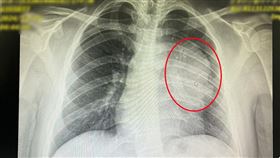

17歲男無症狀竟罹罕癌 健檢驚見12CM腫瘤

台中一名17歲男學生,在學校的例行健檢中,胸腔X光檢...